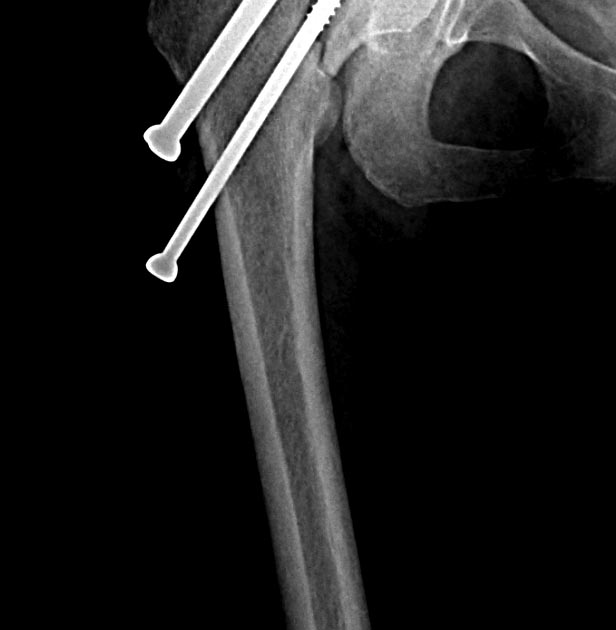

Две несросшихся шейки бедра, пацинтка 27 лет, травме 5 месяцев

Травма 5 месяцев назад кататрвма.

БИОС плеча, Чкдо на л/запястный сустав, Биос левого бедра, Мос правой шейки

бедра винтами.

Причина обращения -выявленный ложный сустав шейки левого бедра. При

дообследовании выявлен несросшийся перелом шейки бедра на винтах.

правой конечностью.Справа остесинтез с коррегирующей остеотомией, но смущает

состояние верхнего полюса после миграции винтов, что может повлечь

протезирование на фоне нарушения анатомии проксимального бедра, что не

хорошо для выживаемости протеза у 27 летней пациентки. Может сразу протез

?КТ головки не информативна из-за винтов

На шейке с шурупами понятно остеотомия и фиксатор с угловой стабильностью, а

слева надо бы определится что с головкой

, живая или нет. Я бы сделал изотопное сканирование с технецием BONE SCAN.